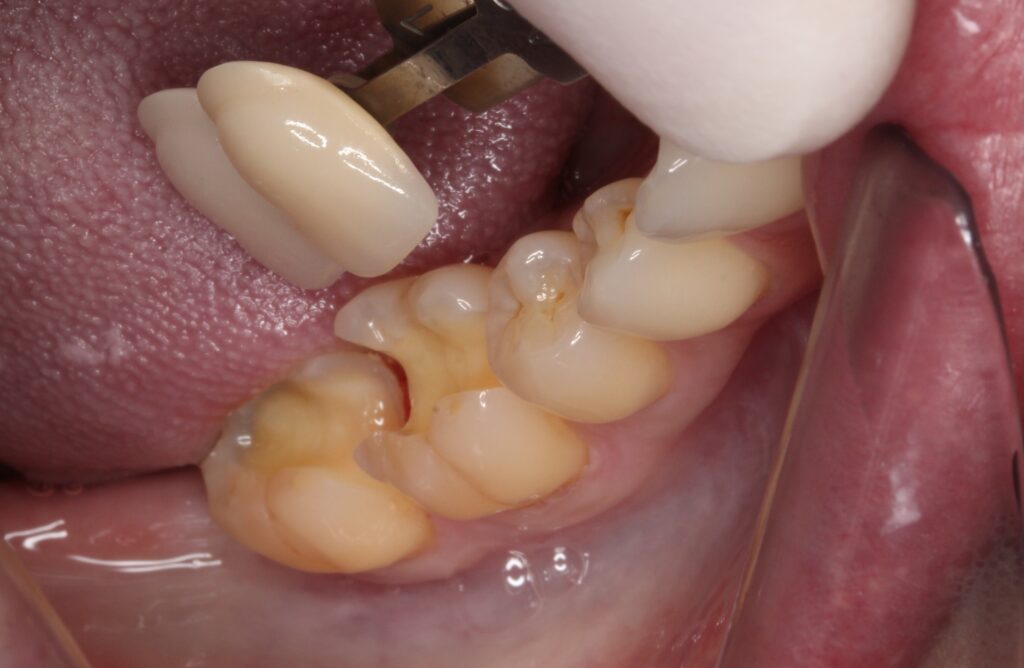

お口の中は、

このような状態です。

一見どこに虫歯があるか分かりません。

虫歯の箇所は、

矢印の所に虫歯があります。

歯と歯の間から侵入しているために表面上は分かりません。

エックス線(レントゲン)検査で確認済みです。

上から削っていくと、

茶色い虫歯がありました。

茶色くなっている箇所が虫歯です。

まだ進行がひどくなかったので、

早めに処置ができましたが、接している両方の歯に侵入が見られましたので、2本の歯の治療が必要となります。